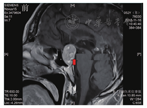

患者男,52岁,于2018年11月1日主诉"中上腹胀痛伴呕吐3 d"入院。入院前3 d无明显诱因出现中上腹胀痛,进食后明显,腹部胀痛时可见上腹部隆起,间断有恶心、呕吐,呕吐物为胃内容物,无隔夜宿食、凝血块和咖啡色物质,呈非喷射性,呕吐后中上腹胀痛可减轻,上腹部隆起可消退,食欲不振,偶感反酸、嗳气,体毛脱落明显,性欲减弱,无呕血、排黑便,无巩膜黄染、尿黄、皮肤黄,无头痛、头晕,无视物模糊,无肢体乏力,无乳腺胀痛、分泌乳汁等不适。拟"消化性溃疡并幽门梗阻?"收入院。体格检查:体温36.5 ℃,脉搏68次/min,呼吸频率20次/min,血压112/70 mmHg (1 mmHg=0.133 kPa),神情疲惫,体毛减少,双侧瞳孔等大、等圆,直径约为3 mm,对光反射灵敏,眼底和视力检查无明显异常。未见男性乳房发育。中上腹部饱满,中上腹轻度压痛,无反跳痛,可闻及振水音,肠鸣音为4~5次/min(正常参考值范围内)。四肢肌力、肌张力正常,病理征未引出。既往曾多次因胃溃疡、十二指肠溃疡发作入住福建医科大学附属三明市第一医院治疗。入院后多次查电解质:血钾波动于3.62~4.48 mmol/L,血钠波动于113.4~138.0 mmol/L,血氯波动于82.1~103.5 mmol/L。血浆渗透压为252.69 mOsm/L。血常规、肝肾功能、血糖、心肌酶、肌钙蛋白I、肌红蛋白、尿常规、血脂、凝血功能+D-二聚体+纤维蛋白降解产物、粪便常规+粪便隐血试验、游离三碘甲腺原氨酸(free triiodothyronine,FT3)、游离甲状腺素(free thyroxine,FT4)、促甲状腺激素(thyroid stimulating hormone,TSH)、CA125、CA19-9、癌胚抗原、甲胎蛋白、血淀粉酶均无异常。皮质醇无异常。血醛固酮0.05 μg/L(正常参考值为0.059~0.174 μg/L)。性激素6项:雌二醇17.0 ng/L(正常参考值为20~400 ng/L),孕酮0.02 μg/L(正常参考值为0.1~18.7 μg/L),促黄体生成素(luteinizing hormone,LH)、卵泡刺激素(follicle-stimulating hormone,FSH)、催乳素、睾酮均无异常。腹部立位片:腹部未见明显异常。心电图检查:窦性心律,窦性心动过缓,完全性右束支传导阻滞。彩色多普勒超声检查:胆囊结石,前列腺结石或钙化灶,肝脏、胰腺、脾脏、肾脏、膀胱、门静脉、肾血管、肾上腺区、腹部大血管声像图均未见明显异常,双侧输尿管未见明显扩张,胰腺和腹部主动脉周围未见明显肿大淋巴结。胃镜检查:胃窦息肉,胃窦溃疡(H2期),十二指肠球部溃疡(H2期),幽门圆形,开闭正常。全腹部CT检查:肝左叶小囊肿,胆囊结石,右肾小结石。头部和双肺CT检查:垂体占位,肿瘤伴出血?(图1)。胸部CT检查未见明显异常。头颅MRI检查:鞍区-鞍上占位,考虑垂体大腺瘤合并出血(大小约为2.7 cm×1.8 cm)(图2、图3)。入院后予艾司奥美拉唑抑酸,氯化钠补钠,营养支持治疗,并行胃肠减压,引流出墨绿色液体,每天量为600~1 100 mL。经上述治疗患者血钠恢复正常,无腹部胀痛、呕吐,生命体征平稳,转神经外科手术治疗,术后CT检查示无出血(图4),术后病理结果示垂体腺瘤(图5)。